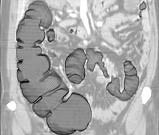

问题 女,56岁,腹胀、腹痛、左下腹包块三月余,无肛门排气,影像检查如图,最可能的诊断是()

选项 A.乙状结肠Crohn病 B.乙状结肠结核 C.乙状结肠腺癌 D.乙状结肠淋巴瘤 E.乙状结肠息肉

答案 C